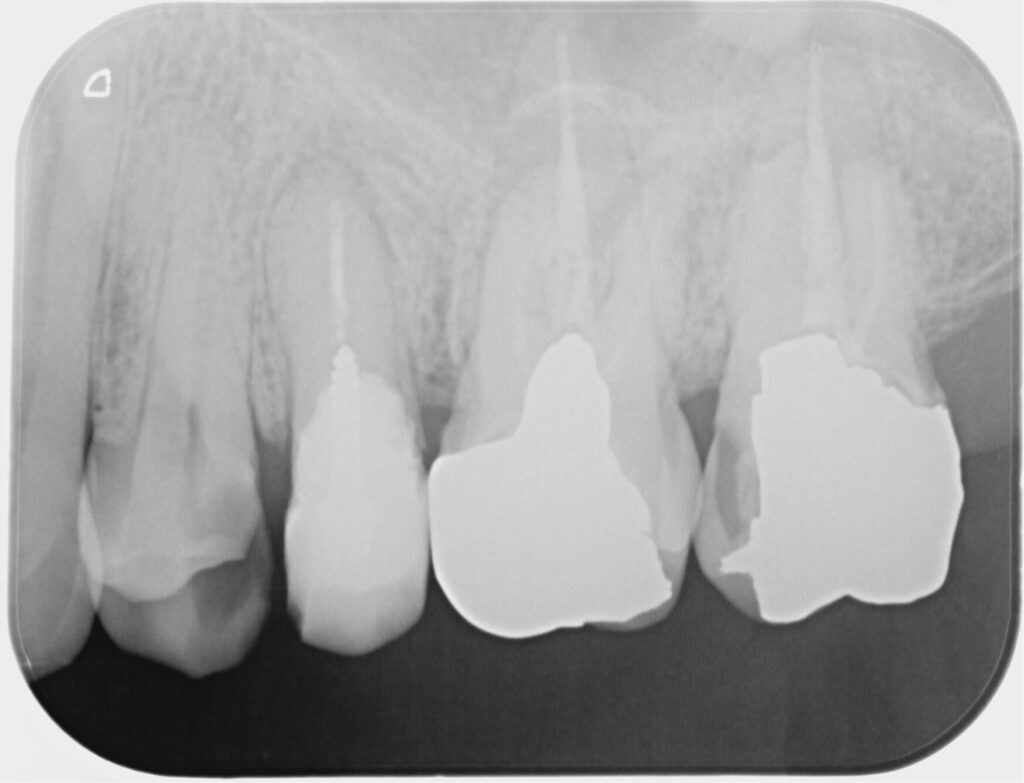

2.初診時の所見

・歯冠部が治療の繰り返しとう蝕によって大きく崩壊(👉治療の繰り返しによるサイクル)

・フェルール(歯ぐきの上の健全歯質)がほぼゼロ

・根尖部に病変/感染の可能性

・このままクラウンを被せても 歯が薄く、破折リスクが極めて高い状態

- フェルール 0mm の歯は噛む力が根に集中し、縦破折(保存不能)が急増する。

- フェルールが 1〜2mm あるだけで、破折リスクが大幅に減少し、予後が安定する。

- Trope らの研究では、ポストの種類より「残存歯質量(フェルール)」が歯の寿命を左右すると示されている。

① 精密根管治療(感染を取り除き、土台を整える)

- マイクロスコープで感染源を徹底的に除去

- 根管形態の把握と破折線の確認

- 根の中を確実に封鎖し、保存可能な状態へ